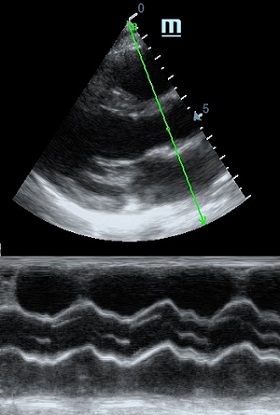

TAPSE - показатель амплитуды движения латеральной части кольца трикуспидального клапана, позволяет количественно и быстро оценить систолическую функцию правого желудочка, норма которого составляет более 17 мм. Главным условием является проведение линии М-режима параллельно стенке правого желудочка в апикальном четырех камерном сечении, что легко достигается при Free Xros.